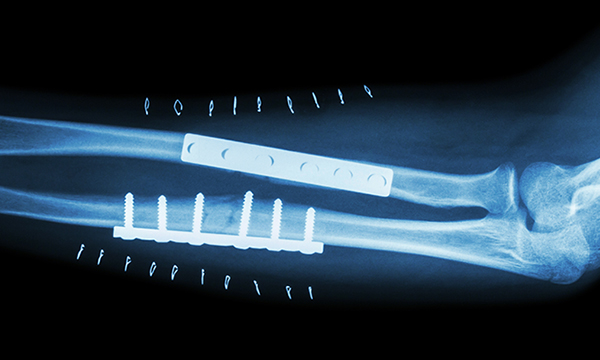

X-Ray 검사

골절선이 지속적으로 보이고, 뼈가 붙지 않은 소견 확인

내고정술 (Internal fixation)